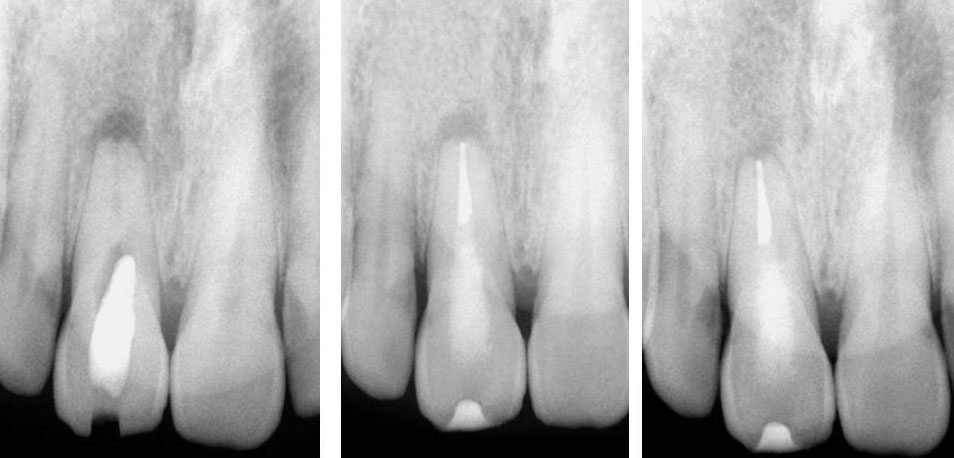

PRE-OP

POST-OP

1 YEAR RECALL

Pre-op, Post-op & One-year recall